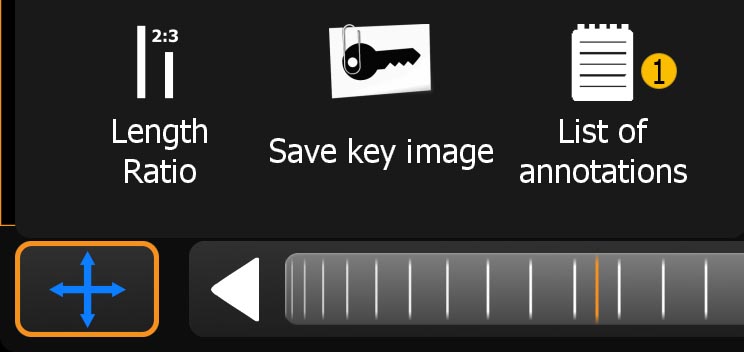

11.1.2. Annotations-Menü

Wenn eine Notiz oder eine Messung erstellt wurde erscheint im Werkzeugmenü folgender Button (siehe Liste der Annotationen).

-

Öffnet das „Liste der Annotationen“-Fenster

-

Einfaches Anklicken wählt die Annotation aus und springt im Betrachtungsfenster direkt zu dieser. Langes Halten eines Eintrags ruft das Untermenü auf (Punkt 2,3).

-

Löschen der ausgewählten Annotation.

-

Name der ausgewählten Annotation bearbeiten.